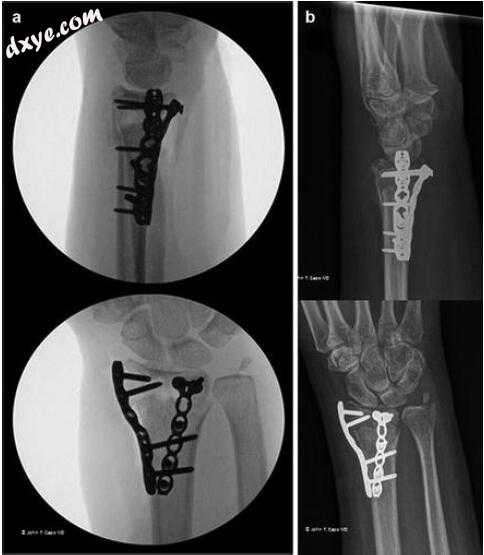

3.jpg

图9.3术后即刻(a)和5周(b)术后X射线。 注意桡骨柱板的相对掌侧位置,板不平行